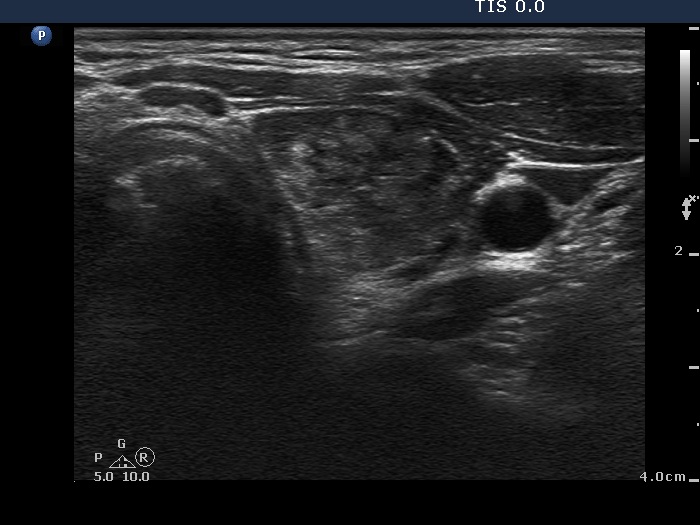

Ethanol sclerotherapy: thyroid cysts - Case 7

First session of therapy (ultrasonographic picture 2)

Upper part of the left lobe, horizontal scan. Corresponding to the underlying Hashimoto's thyroiditis, the extranodular part of the lobe is hypoechogenic and inhomogeneous.